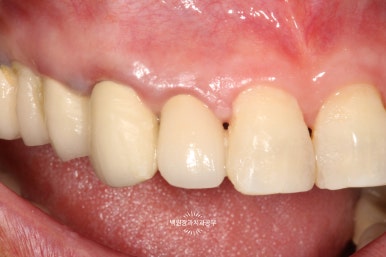

보시는 상태는 외과적 정출술 후 약 3개월이 지난 상태이고 신경치료와 보철치료는 모두 완료되었습니다.

임플란트가 아니라 치아를 이용하여 치료하였기 때문에, 잇몸의 질감과 모양이 살아있어 꽤나 심미적입니다.

(pink esthetic)

치료 전/후를 살펴볼까요?

왼쪽: 오른쪽 위 측절치의 이차우식으로 인한 파절, 오른쪽: 외과적 정출술 2년 뒤

어쨌든 보시면, 왼쪽은 외과적 정출술 (surgical extrusion) 이전의 모습이고 오른쪽은 치료 2년 뒤 모습입니다.

모든 치료 완료 후 1달 뒤 체크업 사진 때보다도 더 잇몸은 자연스러워졌고 매끈한 모습을 보입니다.

치아의 모양과 색상도 적절하여 정말정말 자연스러운 모양을 갖추고 있었습니다.

흔들거림도 거의 없이 환자분이 아주아주 만족해서 사용하시는 경우로 크게 뿌듯함을 느꼈습니다 :)